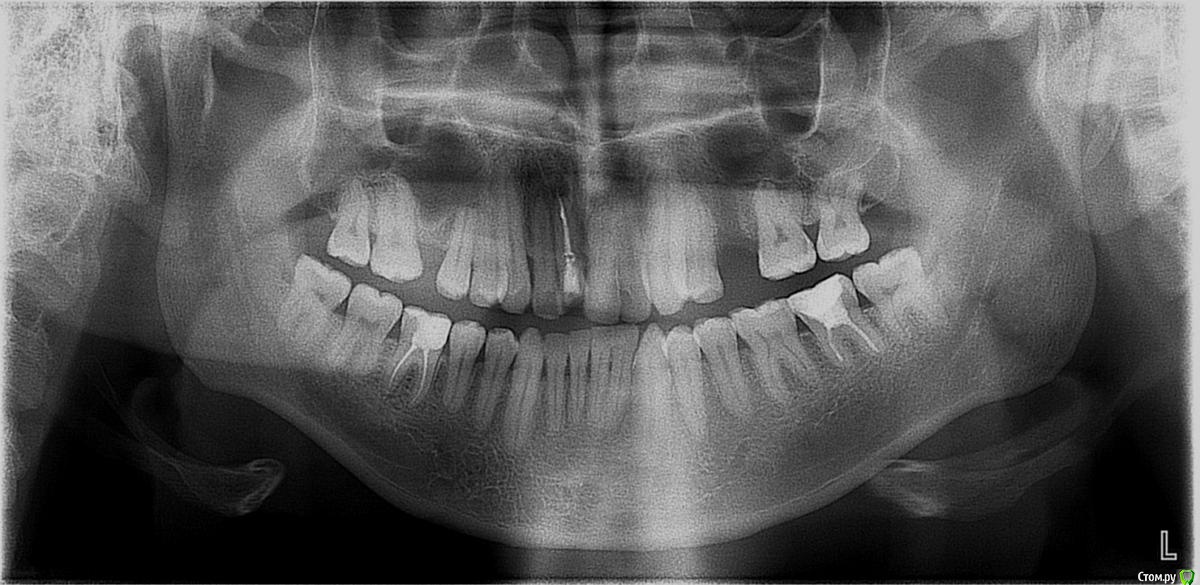

Nick-ev Опубликовано 26 ноября, 2018 Поделиться Опубликовано 26 ноября, 2018 Ношу брекеты уже больше 5ти лет!!!!!!! Очень сильно начали портится зубы, хочу срочно снимать.Вопрос только по правому резцу, он расположен выше левого (не симметрично) врач утверждает, что зуб сточен и опускать его нельзя. Но я то отлично помню, что он поднял его т.к. в него упирался нижний клык, клык давно ушел назад и ничего не мешает выровнять резец. За столько лет я уже не верю никому, но кариес под брекетами дело серьезное. Вопрос, стоит ли выравнивать резец и сколько времени это займет?Было в 13 годуСтало в 18 году Ссылка на комментарий